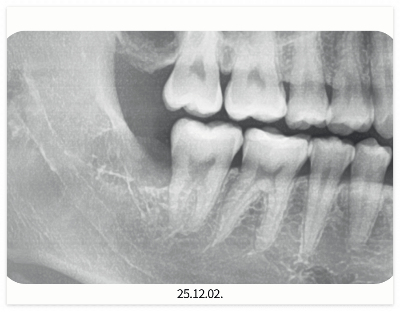

사랑니는 정상적으로 자라나기도 하지만

턱뼈 공간이 부족해

사랑니가 눕거나 매복되어 있는 경우도 많아요.

정상적으로 맹출 된 사랑니는

비교적 쉽게 뽑을 수 있지만

매복된 경우 잇몸을 절개하고

치아를 분리하여 발치해야 합니다.

이 경우 올바른 사랑니보다

출혈량이 많고 지혈도 더 오래 걸릴 수 있죠.